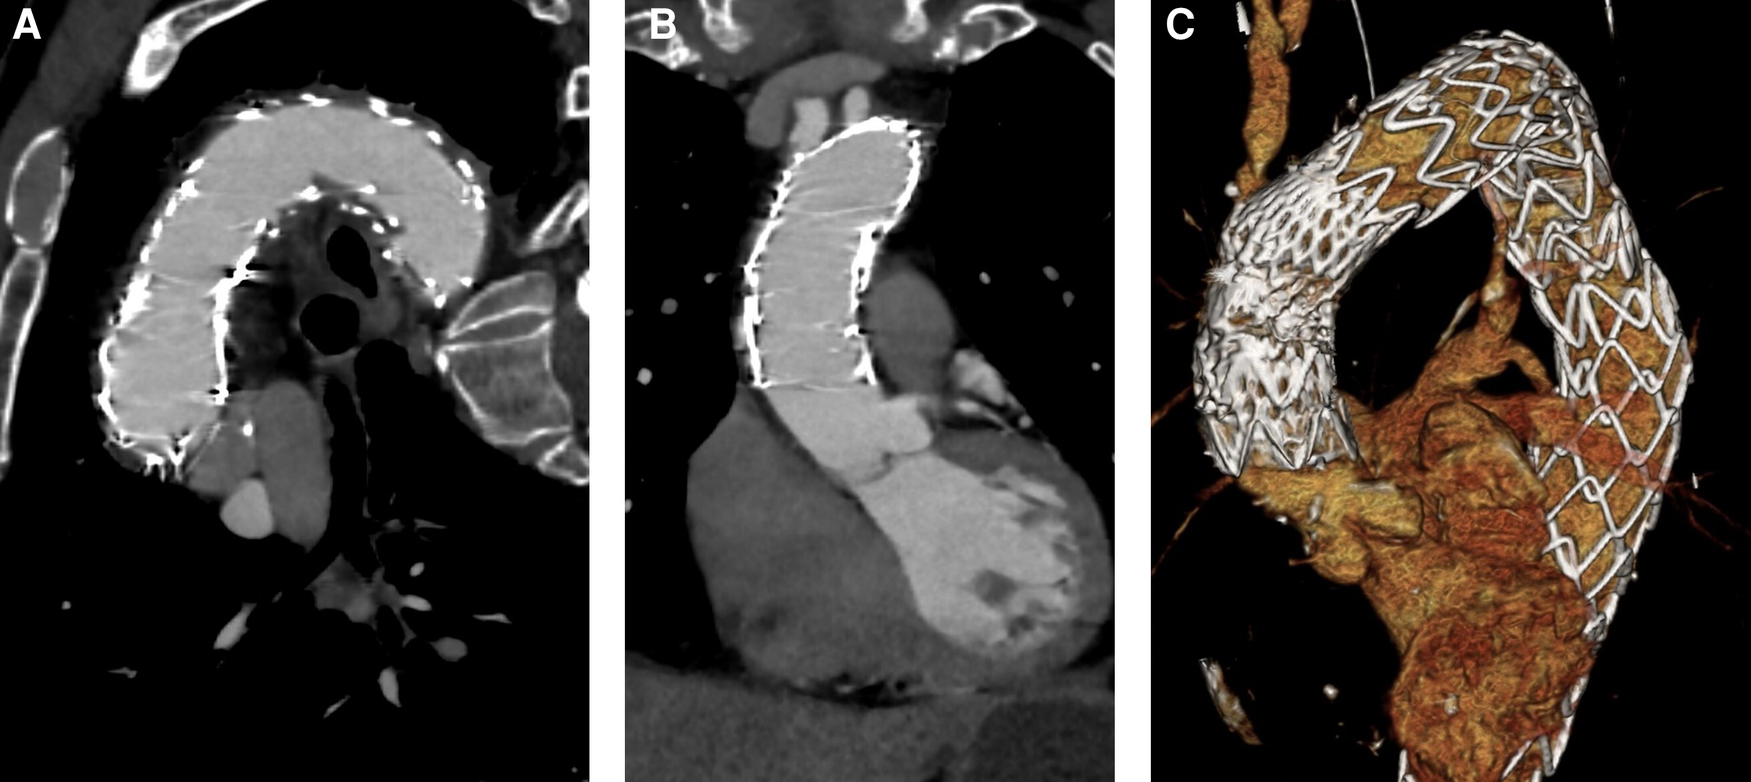

Figure 3

Intraoperative angiography. (A) Aortic dissection after releasing TEVAR stent for proximal expansion. (B) Aortic dissection after stenting of the ascending aorta and parking of a pigtail catheter in the non-coronary cusp. (C) Postoperative result after placing an uncovered stent in the aortic arch (“Reverse PETTICOAT”).

After successfully performing the carotid-subclavian bypass, a 2-cm skin incision was made in the right groin area and the right common femoral artery was punctured percutaneously. Two endovascular closure systems (ProGlide™, Abbott® Cardiovascular, Plymouth, MA, USA) were inserted and prepared for the end of the procedure. Then, a 16-Fr sheath was inserted followed by a flexible wire (Radifocus™, Terumo®, Inchinnan, UK) to pass the aortic valve for pigtail catheter-guided insertion of a pre-bent double curved wire (Safari™, Boston Scientific®, Marlborough, MA, USA), which was placed in the left ventricle. In addition, a temporary pacing electrode was placed in the right ventricle through the right femoral vein. After angiographic control of catheter position and visualization of true and false lumen, the 16-Fr sheath was removed and the stent graft delivery system (Relay® Plus NBS 34/34/109 mm, Terumo®, Inchinnan, UK) was inserted until reaching the aortic arch. After carefully placing the edge of the stent graft delivery system close to the branch of the left common carotid artery (Zone 2), rapid pacing was performed (180/min) and the stent was released. Angiographic control showed adequate expansion and stent position as well as sufficient perfusion of the left common carotid artery. As next step, another thoracic stent graft delivery system (Valiant Navion™ 37/37/55 mm, Medtronic®, Dublin, Ireland) was prepared and inserted until reaching the ascending aorta. Angiographic control was performed precisely to visualize both coronary ostia and the brachiocephalic trunk. Thereby, a 6-Fr pigtail (Boston Scientific®, Marlborough, MA, USA) was parked at the non-coronary cusp considering the radiographic angle to support the identification of the landing zone and avoid protrusion of the stent graft into the coronary arteries. After exact positioning between the coronary ostia and the brachiocephalic trunk, the stent graft was released during rapid pacing (180/min). For further stabilization and aortic remodeling, analogous to the PETTICOAT technique (provisional extension to induce complete attachment), an additional uncovered nitinol stent (E-XL™ 36/07 mm, formerly JOTEC® GmbH, now Artivion®, Hechingen, Germany) was inserted into the aortic arch to connect both stent grafts (11). Angiographic and perioperative transesophageal echocardiography showed satisfactory results with adequate positioning and successful elimination of false lumen flow. The stent graft delivery system including the sheath was removed, and endovascular vessel closure was performed by using the sutures prepared by ProGlide™. Then, the pigtail catheter and sheath were removed from the subclavian-carotid bypass graft. Finally, a redon drainage was placed and the wound was closed in layers finishing with intracutaneous skin suture.

Perioperative transesophageal echocardiography revealed preserved biventricular function, no relevant aortic insufficiency, or any wall motion abnormalities. No persistent flow could be detected in the false lumen. Intraoperative angiographic steps are shown in Figure 3.